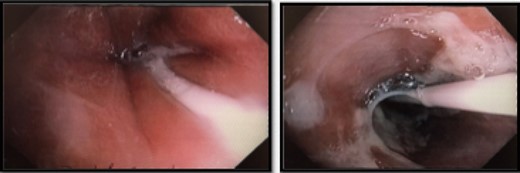

He was commenced on high-dose PPI, IV Antibiotics and analgesia. Emergency gastroscopy showed middle third of esophagus consistent with esophagitis and circumferential ischemia/necrosis in distal esophagus 27–34 cm (Fig. 6). Mucosal biopsies taken revealed ulcerated squamocolumnar mucosa with necrosis and inflammation. No CMV inclusions were identified.

Nasojejunostomy tube was inserted and feeds were commenced. Interval gastroscopy in 2weeks revealed superficial sloughing of esophagus from 27 to 34 cm consistent with partial thickness esophageal necrosis (Fig. 7). Clear fluids were commenced and gradually upgraded to full diet over the course of 6 weeks. Follow-up gastroscopy at 9 weeks showed completely healed mucosa (Fig. 8).

Interval endoscopy at 2 weeks showing signs of healing (Superficial slough at the area of partial necrosis).